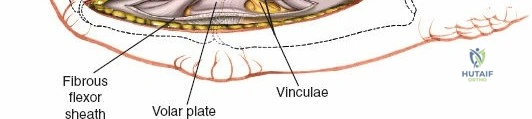

Within the fibro-osseous tunnel, these tendons are enveloped by a synovial sheath that facilitates smooth gliding and nutrition. The integrity of the pulley system, composed of annular (A) and cruciate (C) ligaments, is critical for preventing tendon bowstringing and maintaining efficient mechanical advantage. Typically, five annular pulleys (A1-A5) and three cruciate pulleys (C1-C3) are described in each finger. The A1 pulley is at the metacarpophalangeal (MCP) joint level, A2 at the proximal phalanx, A3 at the proximal interphalangeal (PIP) joint, A4 at the middle phalanx, and A5 at the distal interphalangeal (DIP) joint. The A2 and A4 pulleys are considered the most critical for preventing significant bowstringing.

The palmar fascia, located superficial to the flexor tendons in the palm, is a dense aponeurosis important in conditions like Dupuytren's contracture. This fascial layer can obscure deeper structures and must be carefully managed during deep palmar dissection. The thenar and hypothenar eminences, as well as the transverse palmar crease, serve as important surface landmarks for guiding incisions and identifying underlying structures. The vincula tendinum (longus and brevis) are mesotenon-like structures that provide vascular supply to the flexor tendons within the sheath, and their preservation, where possible, is beneficial.

Once the subcutaneous tissue and neurovascular bundles are retracted, the fibrous flexor sheath is visible. This appears as a glistening white, tough structure enveloping the flexor tendons.

The sheath is incised longitudinally. The specific pulleys that need to be released depend on the pathology and zone of injury.

Once the flexor sheath is opened, the FDS and FDP tendons are exposed.

- Debridement and Preparation: The tendon ends are gently debrided of any frayed or necrotic tissue, ensuring clean, healthy margins for repair. The synovial sheath is preserved where possible.

- Infection Drainage: For pyogenic flexor tenosynovitis, the sheath is incised longitudinally along its entire length, and thorough irrigation with saline solution is performed. Tissue samples are sent for culture.